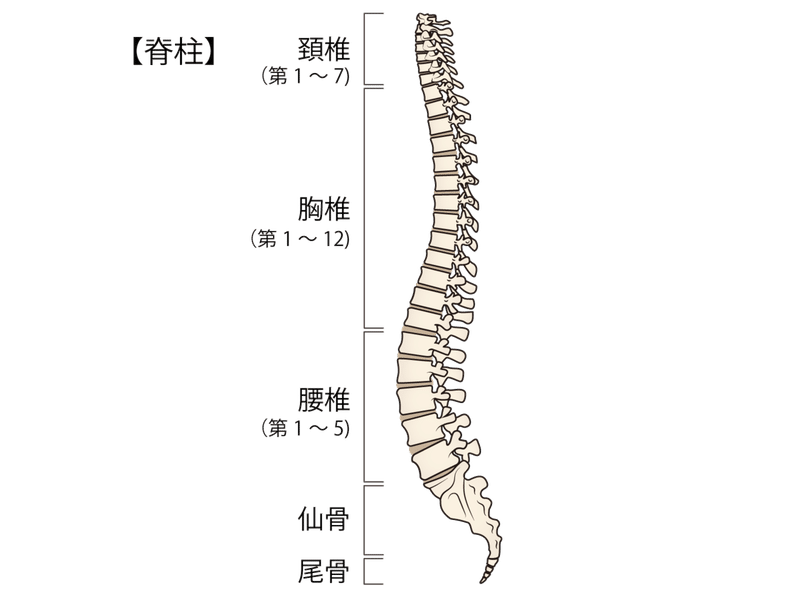

あぐらをかいて座る女性 写真素材フォトライブラリーは、日本のストックフォトサイトです。ロイヤリティーフリー画像を販売。動画素材はsサイズすべて無料。 s550円~ id: あぐらをかいて座る女性 はこちら縁側であぐらをかく和服姿の男性 の写真素材・イラスト素材|アマナイメージズ 縁側であぐらをかく和服姿の男性 の写真素材・イラスト素材。 アマナイメージズでは3000万点以上の高品質な写真素材・イラスト素材・動画素材が購入可能です。 ロイヤリティフリー作品だけでなくライツマネージド作品も豊富に取り揃えています。 椎間板ヘルニアが原因で、あぐらをかいて足がしびれる? あぐらの姿勢は通常、 椎間板ヘルニア の症状が楽になる姿勢なので可能性はとても低いと考えられます。ヘルニアで神経が圧迫されているためにしびれが出ているなら、日常生活のいろいろな場面でしびれや痛みを感じているは

くことにより吸収され、 弱められる。あぐら姿勢で手を膝に置く場合、肘 関節が90度程度に屈曲する。このためあぐらでは、肘関節が身体の揺 れに合わせて動きやすく、呼吸などによる揺れを相殺する働きをしたの ではないかと思われる。あぐらをかいた時に、脚が床につかず、浮いてしまう。両手で膝を押し下げようと頑張っても、脚に力が入り、曲がらない。 あぐらをかいた時、脚が浮いてしまう?/photo by Kentaro Abe 股関節が硬いタイプが苦手なポーズ 股関節が硬い人が苦手なポーズ唱題の姿勢|願い方次第で必ず叶う勤行・題目 について 朝晩の勤行の時に、まず真剣に願いをかけるのです。 自分が願いたいことを順番に紙に書いて、勤行の後の題目の時に、一つずつ自分の生命に叩きこむように真剣に願うのです。 例えて言うなら

日常生活で よくあぐらをかく人は腰痛になりやすいのか らいおんハート整骨院グループ

胡坐 あぐら と腰痛の関係 スポルト鍼灸整骨院 中野店 スポルト鍼灸整骨院 中野店

胡坐 あぐら と腰痛の関係 スポルト鍼灸整骨院 中野店 スポルト鍼灸整骨院 中野店

胡坐 あぐら と腰痛の関係 スポルト鍼灸整骨院 中野店 スポルト鍼灸整骨院 中野店